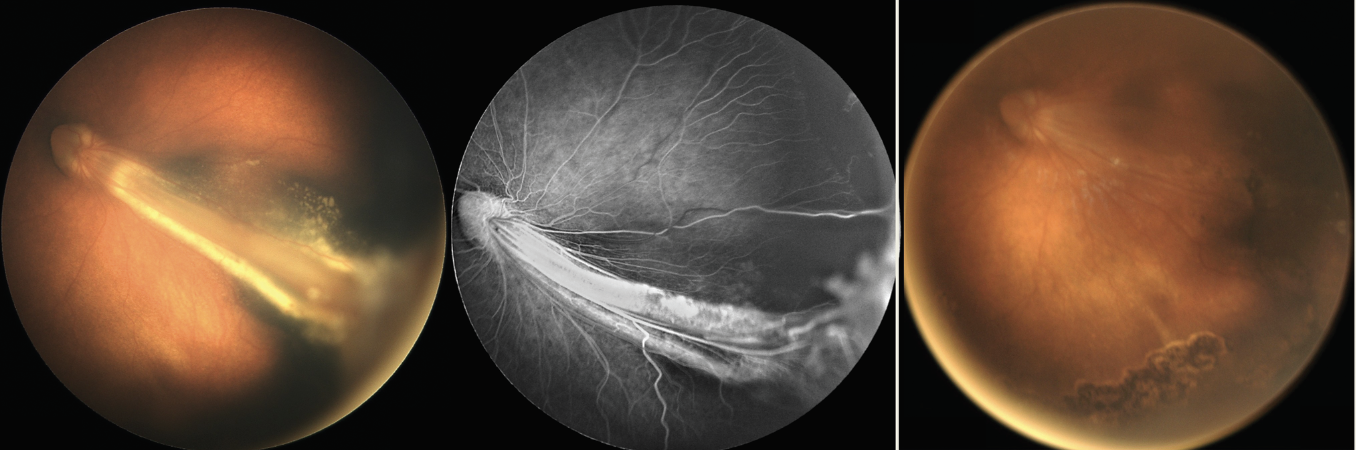

| Figure 3. Familial exudative vitreoretinopathy associated with macular fold, exudation and peripheral nonperfusion (left). Tractional retinal detachment resolved with flattening of macular fold two months after lens-sparing vitrectomy (right). |

Pediatric TRDs are most common in the setting of retinopathy of prematurity, FEVR (Figure 3), and persistent fetal vasculature and, rarely, in incontinentia pigmenti and Norrie disease. Key principles in the management of pediatric TRDs include: